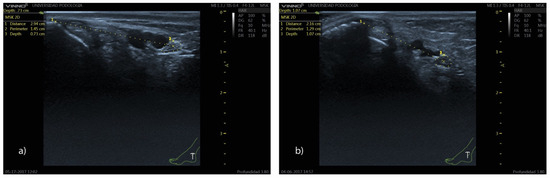

Background: Clinical procedures involving the tibial nerve (TN) are complex procedures due to its deep anatomical position and the variability of its course in the retromalleolar region. Few studies have described the ultrasound characteristics of the TN in vivo. This study aims to describe the ultrasound position of the TN and its relationship with the posterior tibial artery (PTA) at the retromalleolar level, evaluating the influence of sex, weight, height, and body mass index (BMI). Methods: A cross-sectional ultrasound study was performed on 100 volunteers. Anthropometric variables were recorded. Ultrasound measurements included the TN perimeter, distance from the medial malleolus to the TN center, depth, and spatial relationship with the PTA. Statistical analyses included Student’s t-test, ANOVA, Chi-square test, and Pearson’s correlation coefficient, with a significance level of p < 0.05. Results: The mean distance from the TN to the medial malleolus was 2.17 cm, and its mean depth was 0.91 cm. The most common anatomical pattern was Type I (TN posterior to the PTA) (60%). Sex influenced TN position, with men showing greater distances from the medial malleolus to the TN center (2.42 vs. 1.99 cm) and women showing greater depth from the skin surface to the upper edge of the tibial nerve perimeter (0.94 vs. 0.86 cm). Weight (p = 0.004), height (p < 0.001), and ankle circumference (p = 0.006) correlated significantly with TN location, whereas BMI did not (p = 0.253). Conclusion: These findings provide clinically relevant reference data that may improve the precision and safety of different tibial nerve procedures. Full article